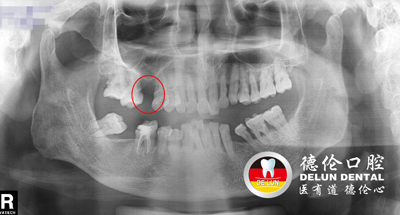

梁先生术前牙齿X光片,上颌下颌均有缺牙

程武主任表示,患者梁先生的缺牙不是一朝一夕的事情,大家可以看梁先生的牙片,下颌由于缺牙多年,相邻两侧的牙齿失去了支持,会在咀嚼力的作用下向缺隙处移位倾倒,出现间隙,容易导致塞牙、咬合系统紊乱等。